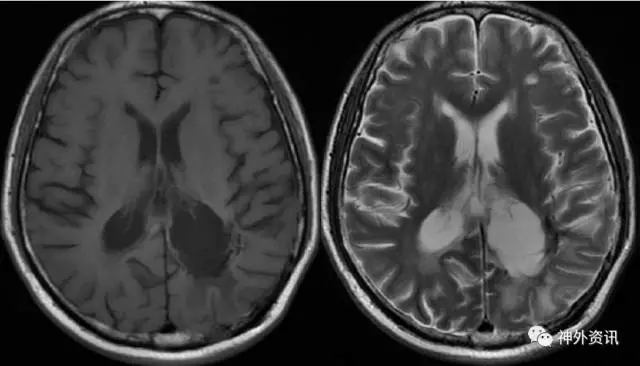

辅助检查:增强MRI示(2016.7.12):左侧顶枕骨术后改变,左侧脑室后角旁不规则形异常信号,大小约37mm*46mm*39mm,呈T1、T2等信号,内见小片T2稍高信号,增强后呈明显强化,强化尚均匀,周边见大片T1低信号、T2高信号水肿区,左侧颞叶及右侧脑室后角旁见小片类似强化信号,左侧侧脑室受压,双侧脑室前后角旁及半卵圆中心、左侧额叶见多发点片状长T2高信号。影像诊断:左侧顶枕骨术后改变,左侧脑室后角旁旁、左侧颞叶、右侧脑室后角旁淋巴瘤复发。两侧脑室前后角旁及半卵圆中心多发缺血灶。左侧额叶囊性病变(图3)。血化验未见明显异常。浅表淋巴结超声、胸片、心电图等相关检查均未见明显异常。

图3. MRI检查:左侧脑室后角旁不规则形异常信号,大小约37mm*46mm*39mm,呈T1、T2等信号,增强后呈明显强化,强化尚均匀,周边见大片T1低信号、T2高信号水肿区。